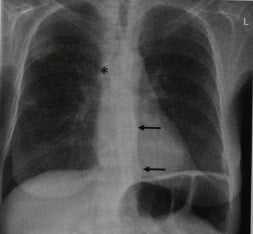

Инфаркт легкого у женщины 47 лет с недостаточностью протеина S. На обзорной рентгенограмме грудной клетки виден клиновидный участок слабо выраженного затемнения в базальном отделе и второй участок затемнения меньших размеров в среднем отделе правого легочного поля, соответствующие инфарктной пневмонии. У больной в анамнезе тромбоэмболический синдром, который вызвал окклюзию нижней полой вены. В результате развития коллатерального кровообращения расширилась непарная вена (звездочка, стрелки).